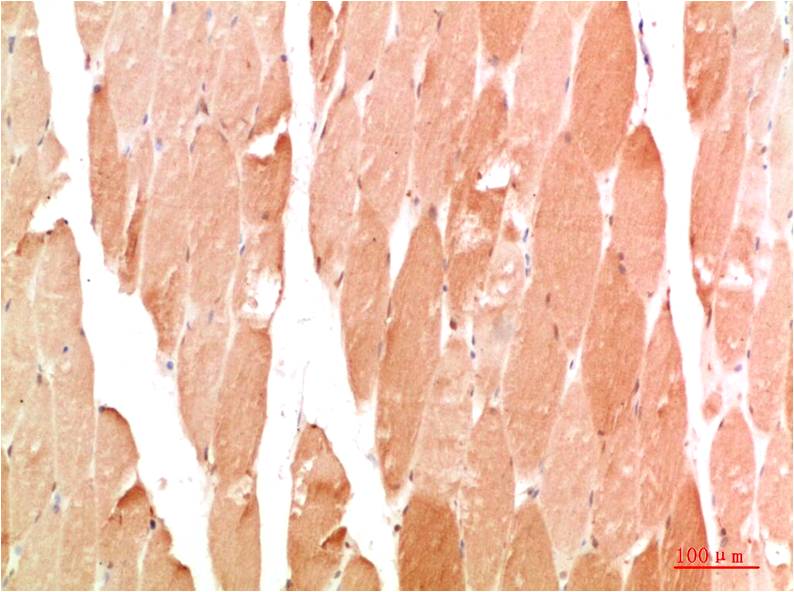

Acetyl P53(K382) Mouse Monoclonal Antibody(5H10)

Applications :IHC

| Recommended dilutions: | IHC: 1:100-200 |

| Specificity: | The Acetyl P53(K382) Mouse Monoclonal Antibody can detects endogenous Acetyl P53(K382) proteins. |